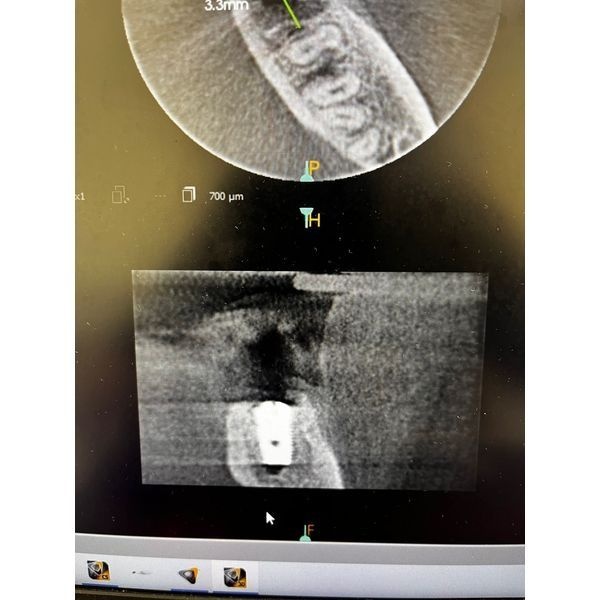

- провели контрольную КТ.